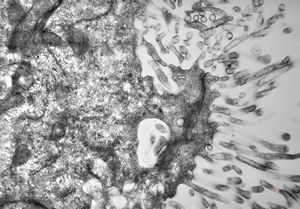

F,50y. | progressive multifocal leukoencephalopathy- viral particles in a glial cell